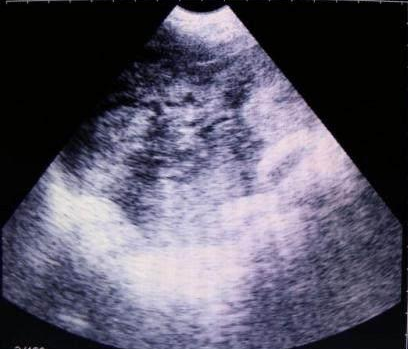

獸用B超機檢測母豬空懷圖像

需要注意的是,出現云團狀必須雙側檢查加以確認.根據B超機顯示圖我們大致可以判斷孕齡.圖像呈橢圓或者卵圓形大致為30天左右孕齡;圖像呈橢圓形或者卵圓形外,有明顯發亮骨骼圖像大致為50孕齡左右;圖像囊胚消失,發亮處隱約可見竹節狀東西為成型胎兒骨骼,一般為后期80孕齡以后。一般B超機成像會出現三種顏色,白色、黑色、灰色。白色為密度較高的物體,如骨骼或者結實.黑色一般為液體,包括血液、羊水、組織間隙液體、炎癥病灶等。灰色一般為實質性物質,如肌肉。